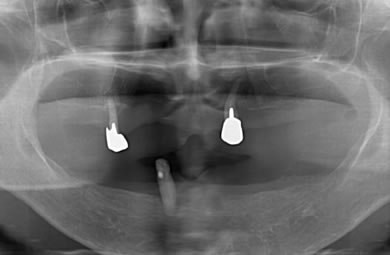

インプラントの症例写真 IMPLANT

骨再生スピードインプラント治療+AGC連結セラミック治療

| 性別/年齢 | 女性 / 57歳 | ||||||||||||||||||||||||||||||||

| 治療内容 | インプラント12本(サイナスリフト+GBR+抜歯即日スピードインプラント+遊離歯肉移植)、AGCハイブリッドセラミック連結ブリッジ2装置(上顎・下顎)、テンポラリーインプラント2本 | ||||||||||||||||||||||||||||||||

| 総治療費 | 6,019,650円 | ||||||||||||||||||||||||||||||||

| 治療期間 | 1年0ヶ月 |